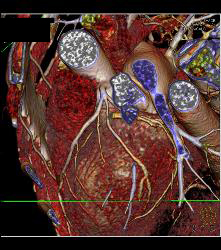

Normal Left Anterior Descending Coronary Artery (LAD)